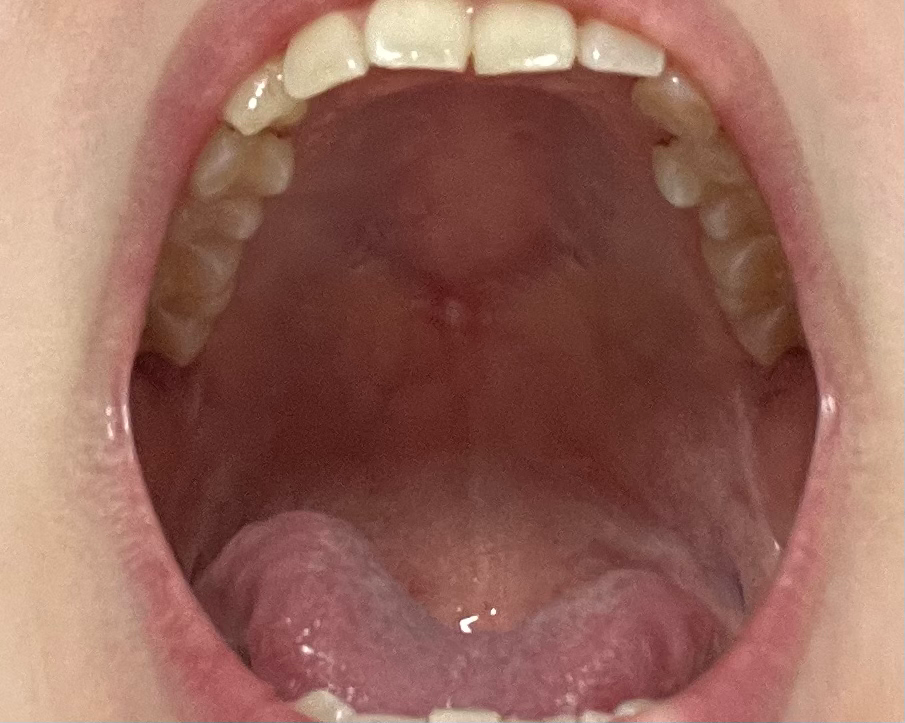

입천장 통증과 혹 구강암 일까요?

몇년동안 가끔 혀를 굴리다보면 느껴졌었는데 원래 있는건줄 알았어요.. 거울로 확인해보니 하얗게 정중앙에 있네요 누르면 아프고 평평하지 않고 볼록 튀어나와있어요 장기간동안 안없어지고 이상태이면 암일까요?

• 2번 째 사진